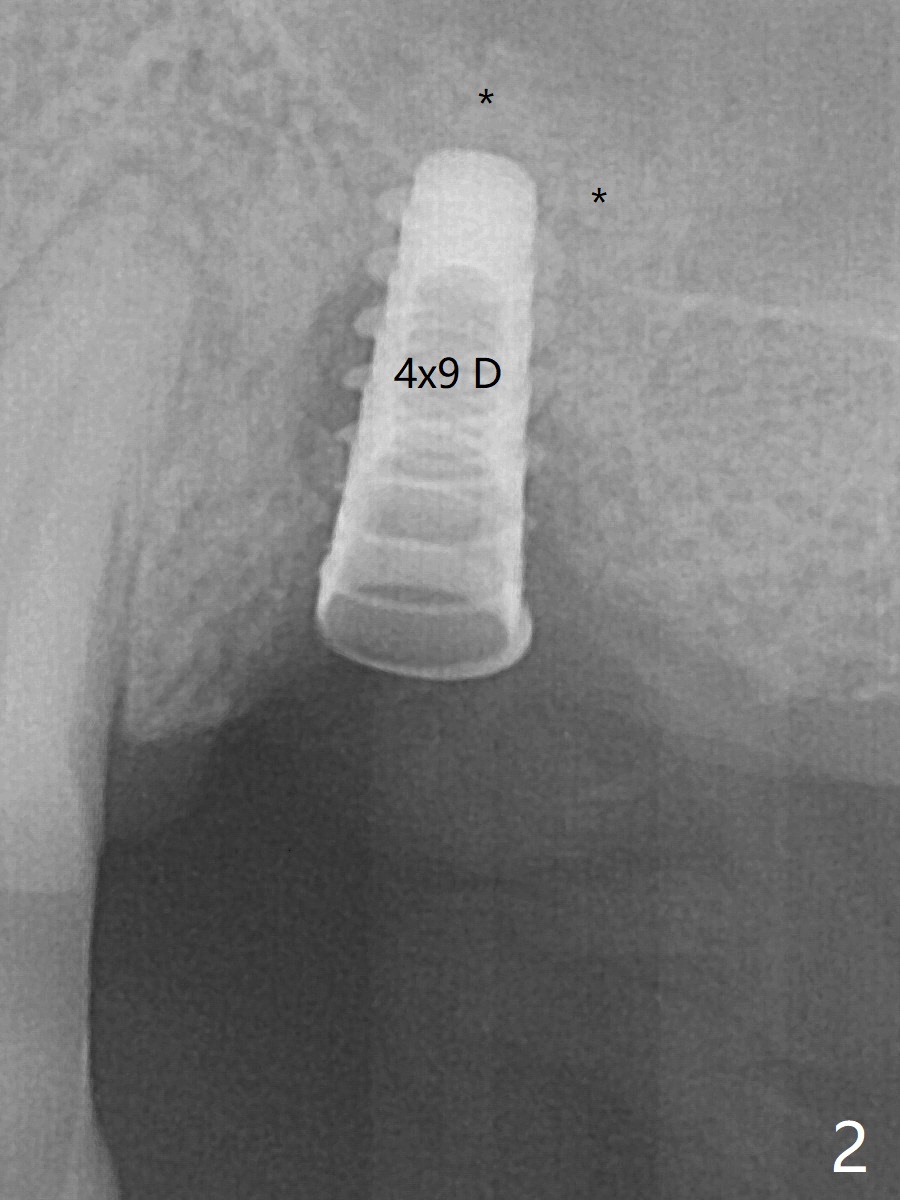

Five months post implant removal and bone graft, incision is made at #12. Osteotomy is being done with guide until 3.0x7.3 mm drill with 1 O-ring (palatal wall being thin), followed by 3.2x17-19 mm sinus round drills and 2.2x11.5 mm drill. After placement of 2 small loads of bone graft, a 4x9 mm dummy implant is inserted for sinus lift (Fig.1,2 *). By this time, the buccal plate is gone, while there is apparently the palatal periosteum. With more bone graft for sinus lift, a 4x9 mm final implant is placed with 30 Ncm (machine) and 4 mm subgingival (Fig.3,4 double arrows). Sticky bone (Fig.5,6 *) is applied around the coronal end of the implant and cover screw (S), followed by 2 pieces of PRF and 4-0 PGA suture. The sutures appear to have been dissolved and PRF membrane exposed 7 days postop (Fig.7,8 (smoker)). Four months postop, the wound heals except a small hole, which seems to be communicated with the underlying implant (Fig.9). The sinus lift remains (Fig.10 <), while bone loss appears to be present around the implant (Fig10,11 *). After placement of 5.5x4 mm healing abutment and before suturing, allograft is pushed into periimplant space (Fig.12, 13 *).